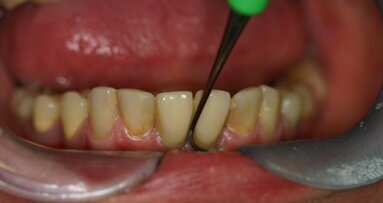

38-letni pacjent, ogólnie zdrowy, niepalący zgłosił się w celu uzupełnienia braku zęba 11. Mężczyzna został pobity, w wyniku czego doszło do złamania korony zęba 21 oraz złamania korony i korzenia zęba 11 (Ryc. 1).

Ze względu na inne obrażenia ciała zaplanowano ekstrakcję oraz wczesną implantację. Ząb 11 został usunięty, a zębodół zaopatrzono Biocollagenem (Ryc. 2). Ząb 21 odbudowano oraz opracowano pod uzupełnienie tymczasowe (Ryc. 3). Po 8 tygodniach przystąpiono do zabiegu implantologicznego. Po odpreparowaniu płata stwierdzono ubytek policzkowej blaszki kostnej (Ryc. 5). Przygotowano łoże implantu w obrębie okna estetycznego (Ryc. 6) i wprowadzono implant BEGO Semados S 4, 1L 13 (Ryc. 7 i 8). Wykonano augmentację biomateriałem BEGO Oss, który pokryto błoną kolagenową BEGO Membrane w technice dwuwarstwowej (Ryc. 9 i 10). Ranę zaszyto szwami nieresorbowalnymi.

Po 6 miesiącach od zabiegu odsłonięto implant i uwidoczniono nową, odbudowaną biomateriałem kość (Ryc. 11). Wykonano koronę tymczasową na łączniku tymczasowym w celu kształtowania dziąsła (Ryc. 12 i 13). Po 3 tygodniach wykonano transfer indywidualny oraz przystąpiono do wykonania ostatecznej pracy protetycznej opartej na łączniku cyrkonowym oraz korony 21 na podbudowie cyrkonowej (Ryc. 14-17).